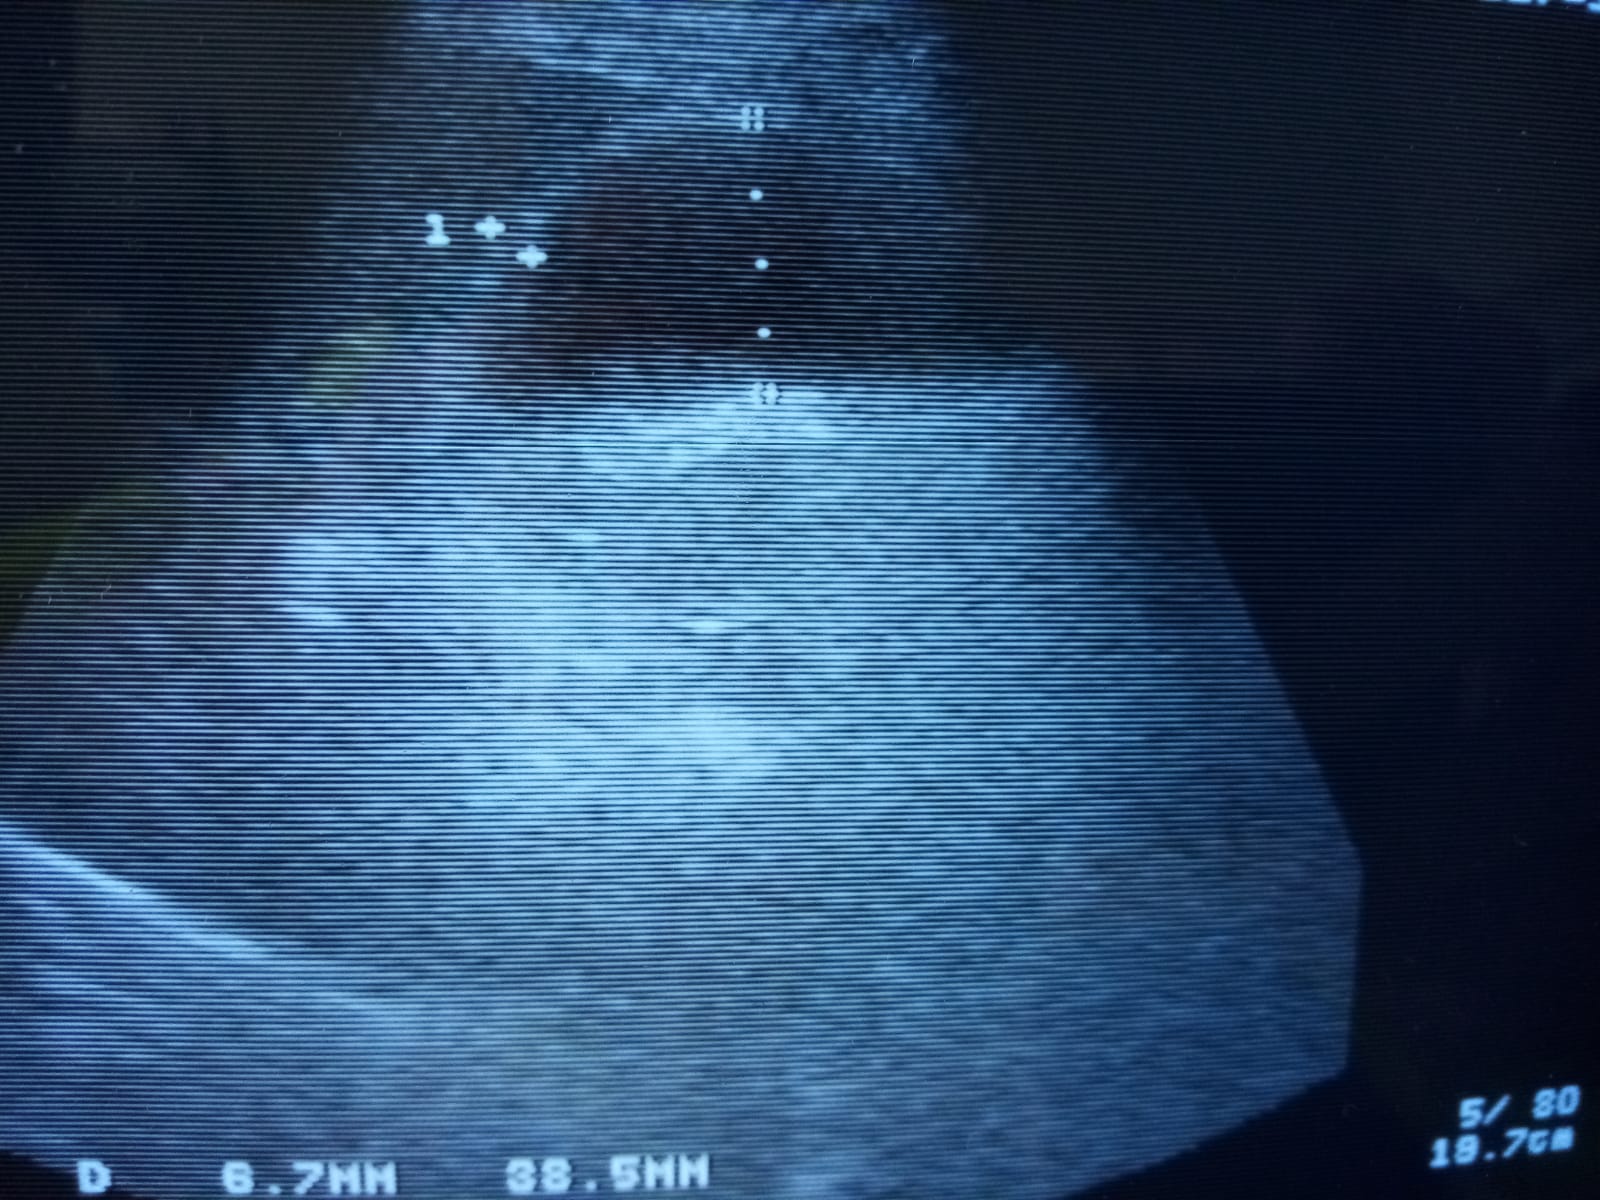

Vesícula biliar de tamaño conservado (38,5 mm), pared engrosada (6,7 mm), contenido biliar significativo, alitiásica.